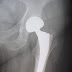

Пацієнтка 67 років. Рентгенограма органів грудної клітки в прямій проекції. Легені - негомогенне затінення в нижніх відділах зліва без чітких контурів. Корені ущільнені. Синуси вільні. Серце розширено вліво.

Заключення: Лівобічна нижнєдольова пневмонія(з анамнезу - коронавірусна інфекція).